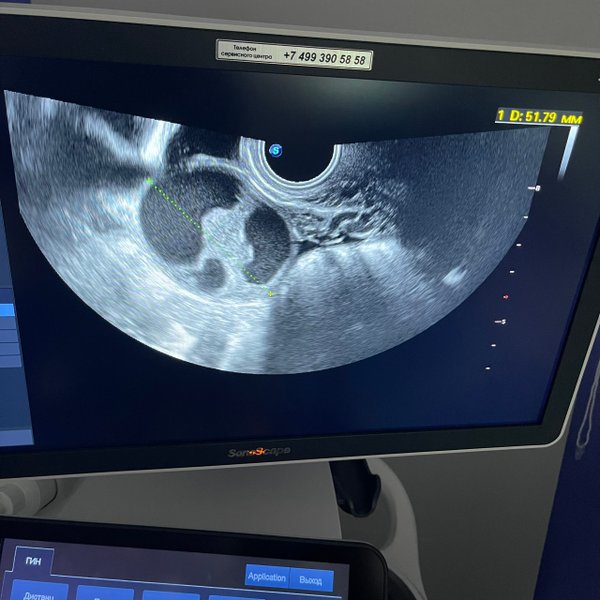

УЗИ диагностика. ️По записи Без очереди ⏰Ежедневно с 10:00 до 17:00 ️Перерыв с 13:00 до 14:30 ️Суббота с 10:00 до 15:00 ‼️Воскресенье ВЫХОДНОй --- Бородулина Наталья (Врач УЗИ, Косметология) (09.12.2025): Киста желтого тела на #УЗИ при беременности.. . . Это НЕ страшно‼️Это вариант нормы при беременности ️ Представьте себе, что ваш #яичник — это маленькая фабрика по производству гормонов. Когда наступила беременность, на этой фабрике образуется временный «гормональный завод» — желтое тело. Его задача — вырабатывать #прогестерон, главный… — Читать дальше

гормон, который сохраняет беременность на ранних сроках. Иногда этот «завод» работает слишком активно и на нем образуется маленький мешочек с жидкостью — это и есть #киста желтого тела. Что делать и на что обратить внимание Расслабиться и порадоваться беременности ️ ️ ️Самый важный пункт. Следовать рекомендациям врача. Обычно просто наблюдают. Избегать ️резких движений, подъема тяжестей и интенсивного спорта (чтобы киста не лопнула от перенапряжения, хотя такое бывает редко).

Бородулина Наталья (Врач УЗИ, Косметология) (19.11.2024): Киста яичников на УЗИ: что нужно знать #Кистаяичников — это довольно распространенное явление, которое часто обнаруживается во время #узи исследования. #Киста — это заполненное жидкостью образование, которое может развиваться на поверхности яичника или внутри его. Большинство кист являются доброкачественными и не вызывают серьезных проблем. Виды кист: 1. Функциональные кисты- возникают в результате менструального цикла и обычно исчезают сами по себе. 2. Патологические кисты — могут по… — Читать дальше

требовать медицинского вмешательства. #УЗИ позволяет: — Определить наличие кисты — Исследовать ее размеры и структуру — Оценить, есть ли злокачественные изменения Что делать после обнаружения кисты? — Консультация у врача — важно обсудить результаты УЗИ и узнать, нужны ли дальнейшие обследования. — Наблюдение — в большинстве случаев лечение кист консервативное или просто наблюдение. — Лечение — если киста вызывает симптомы или вызывает беспокойство, врач может предложить медицинское вмешательство. Не игнорируйте симптомы и регулярно проходите обследования, чтобы поддерживать свое здоровье! ️ ️